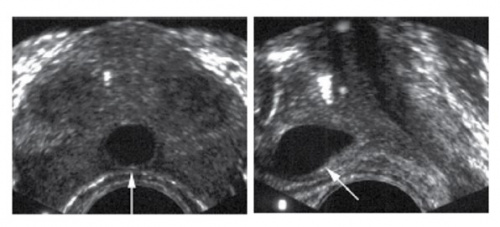

HoLEP 수술 전후

• 전립선석회화(calcification)는“ surgical capsule” 또는 요도 주변에서 주로 관찰된다.